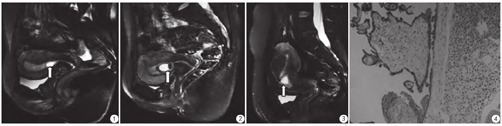

本组38例患者中有28例CSP在磁共振上表现为单纯囊性妊娠囊,呈类圆形、椭圆形的长T1WI长T2WI信号,境界清晰;10例表现为混杂包块型妊娠囊,MR上为类圆形、团状长T1WI、高低混杂T2WI信号(图1,图2,图3,图4);混杂包块型较单纯囊性妊娠囊有更大的最大径、孕囊体积以及与子宫疤痕相交长度,且差异具有统计学差异(P<0.05) (表1)。

本研究中,在MR Sag T2 Fs序列上可清晰显示孕囊位于子宫下段前壁,分为单纯囊性及混杂包块型孕囊。单纯囊性孕囊境界清晰,信号尚均匀,最大径在(2.3±1.2) cm之间波动;包块型孕囊境界欠情,信号混杂、不均,最大径在(4.7±1.3) cm之间波动,且具有统计学差异。包块型孕囊可能与孕周较长,囊内存在绒毛、血凝块有关[12]。单纯囊性孕囊与子宫下段疤痕相交长度在(0.9±0.5) cm之间波动,包块型孕囊与子宫下段瘢痕相交长度在(2.3±0.8) cm之间波动,包块型孕囊植入肌层较深、范围较广;孕囊植入肌层时,肌层变薄,甚至穿透子宫浆膜层、与膀胱壁分界不清。囊性孕囊距子宫浆膜面距离在(0.4±0.4) cm之间,包块型孕囊距子宫浆膜面距离在(0.2±0.2) cm之间波动,然而统计学无差异,可能与样本量过小有关。